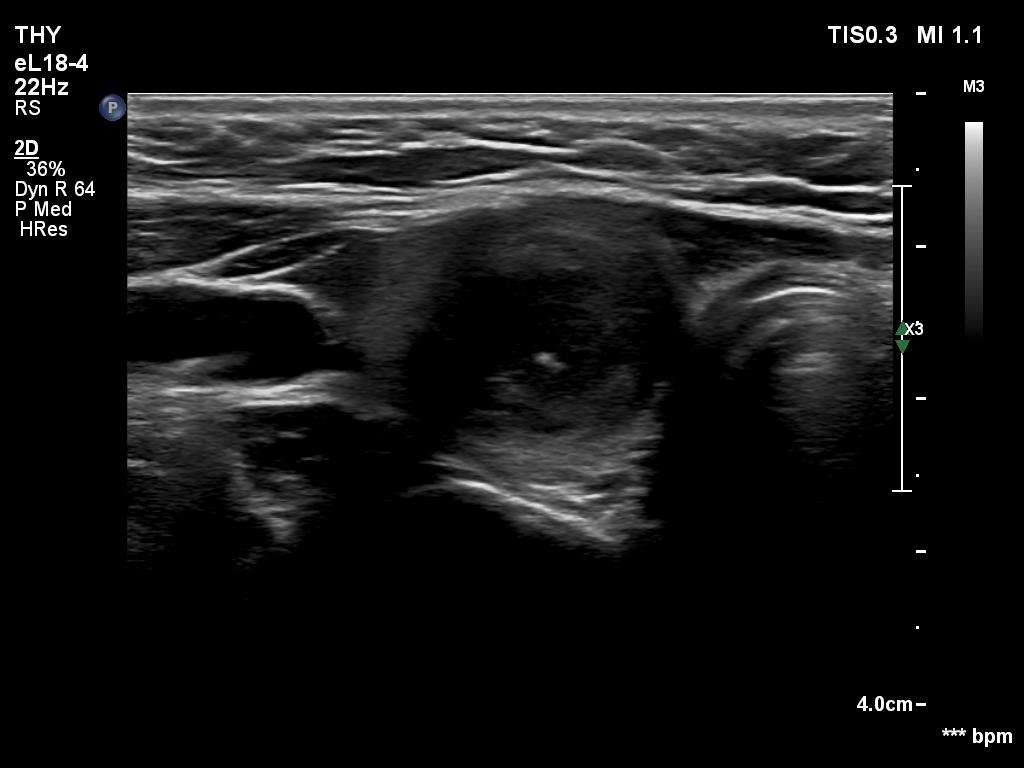

Ultrasonography revealed an echonormal thyroid. There was dominantly moderately hypoechoic nodule in the right lobe. Some parts of the lesion were deeply hypoechoic, and a few small cystic chambers were also within. The nodule presented with irregular shape and borders and had intranodular echogenic figures, primarily granules.

It is ambiguous how to interpret the echogenic figures. Although the presence of irregular shape and borders increases the likelihood that the echogenic granules are indeed microcalcifications, comet-tail artifacts must be also considered.

It is worth comparing the images recorded by using different settings. By using harmonization, we lose the details of very hypoechoic areas. Essentially, the latter seem to be anechoic.